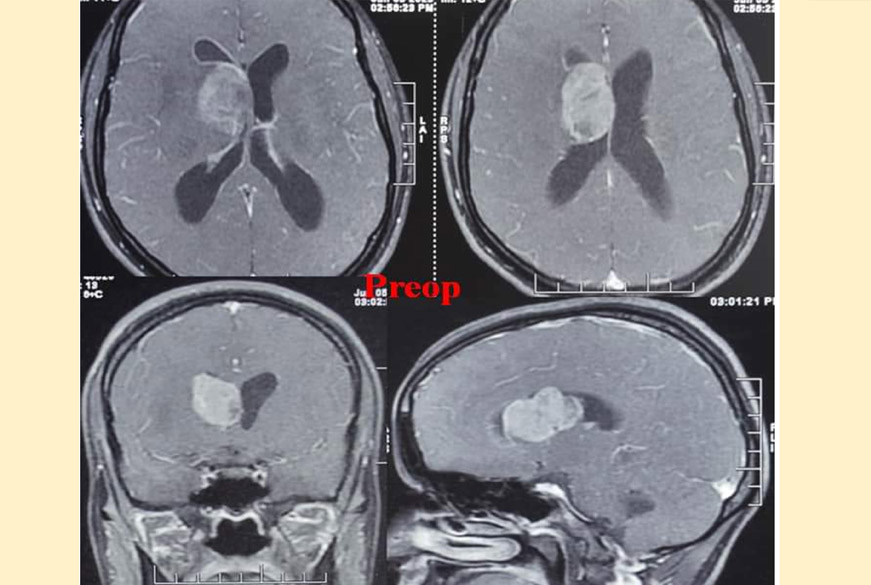

Awake Craniotomy is a technique by which brain surgeries are performed especially in important brain regions where any damage may lead to major impact on patient's physical condition...